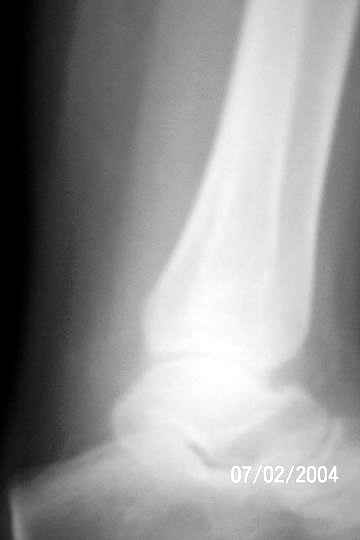

Giant cell tumor

I am attaching an x-ray of 36 - years- old female patient had a cystic lesion with left fibula.

1 yrs back-curettage and bone-grafting elsewhere, for cystic lesion.

Biopsy report: Giant cell tumor – Grade 2

I would appreciate your inputs regarding this case.